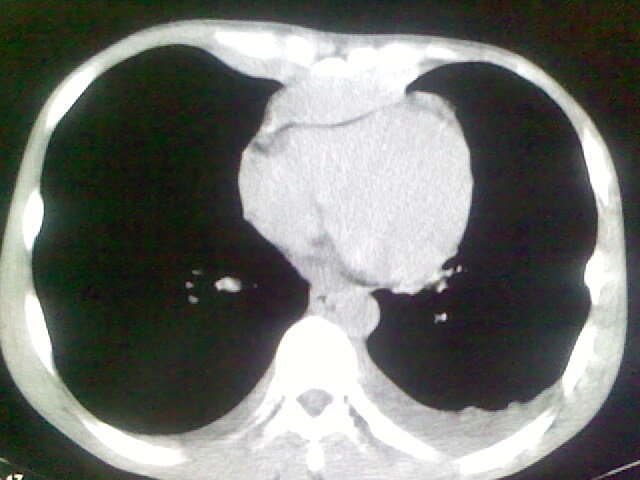

以下是引用杀毒软件在2008-9-3 6:11:00的发言:[br]侵袭性胸腺瘤------一般不侵到气管旁[br][br]考虑----纵隔淋巴瘤,心包及胸膜受累

以下是引用wzr在2008-9-3 5:30:00的发言:[br]侵袭性胸腺瘤

以下是引用随光逐影在2008-9-3 7:07:00的发言:[br]1)考虑淋巴瘤可能。2)双侧胸腔积液(以左侧为甚)。3)心包积液。